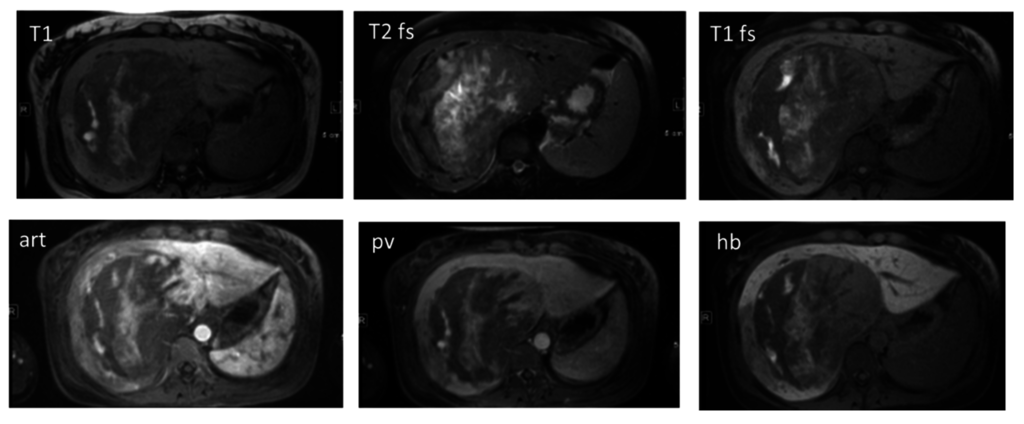

3. Magnetic Resonance Imaging (MRI)

3.1. Hepatocyte Specific MRI Contrast Agents

3.2. Diffusion-Weighted MR Imaging

3.3. Dynamic Contrast Enhanced MRI